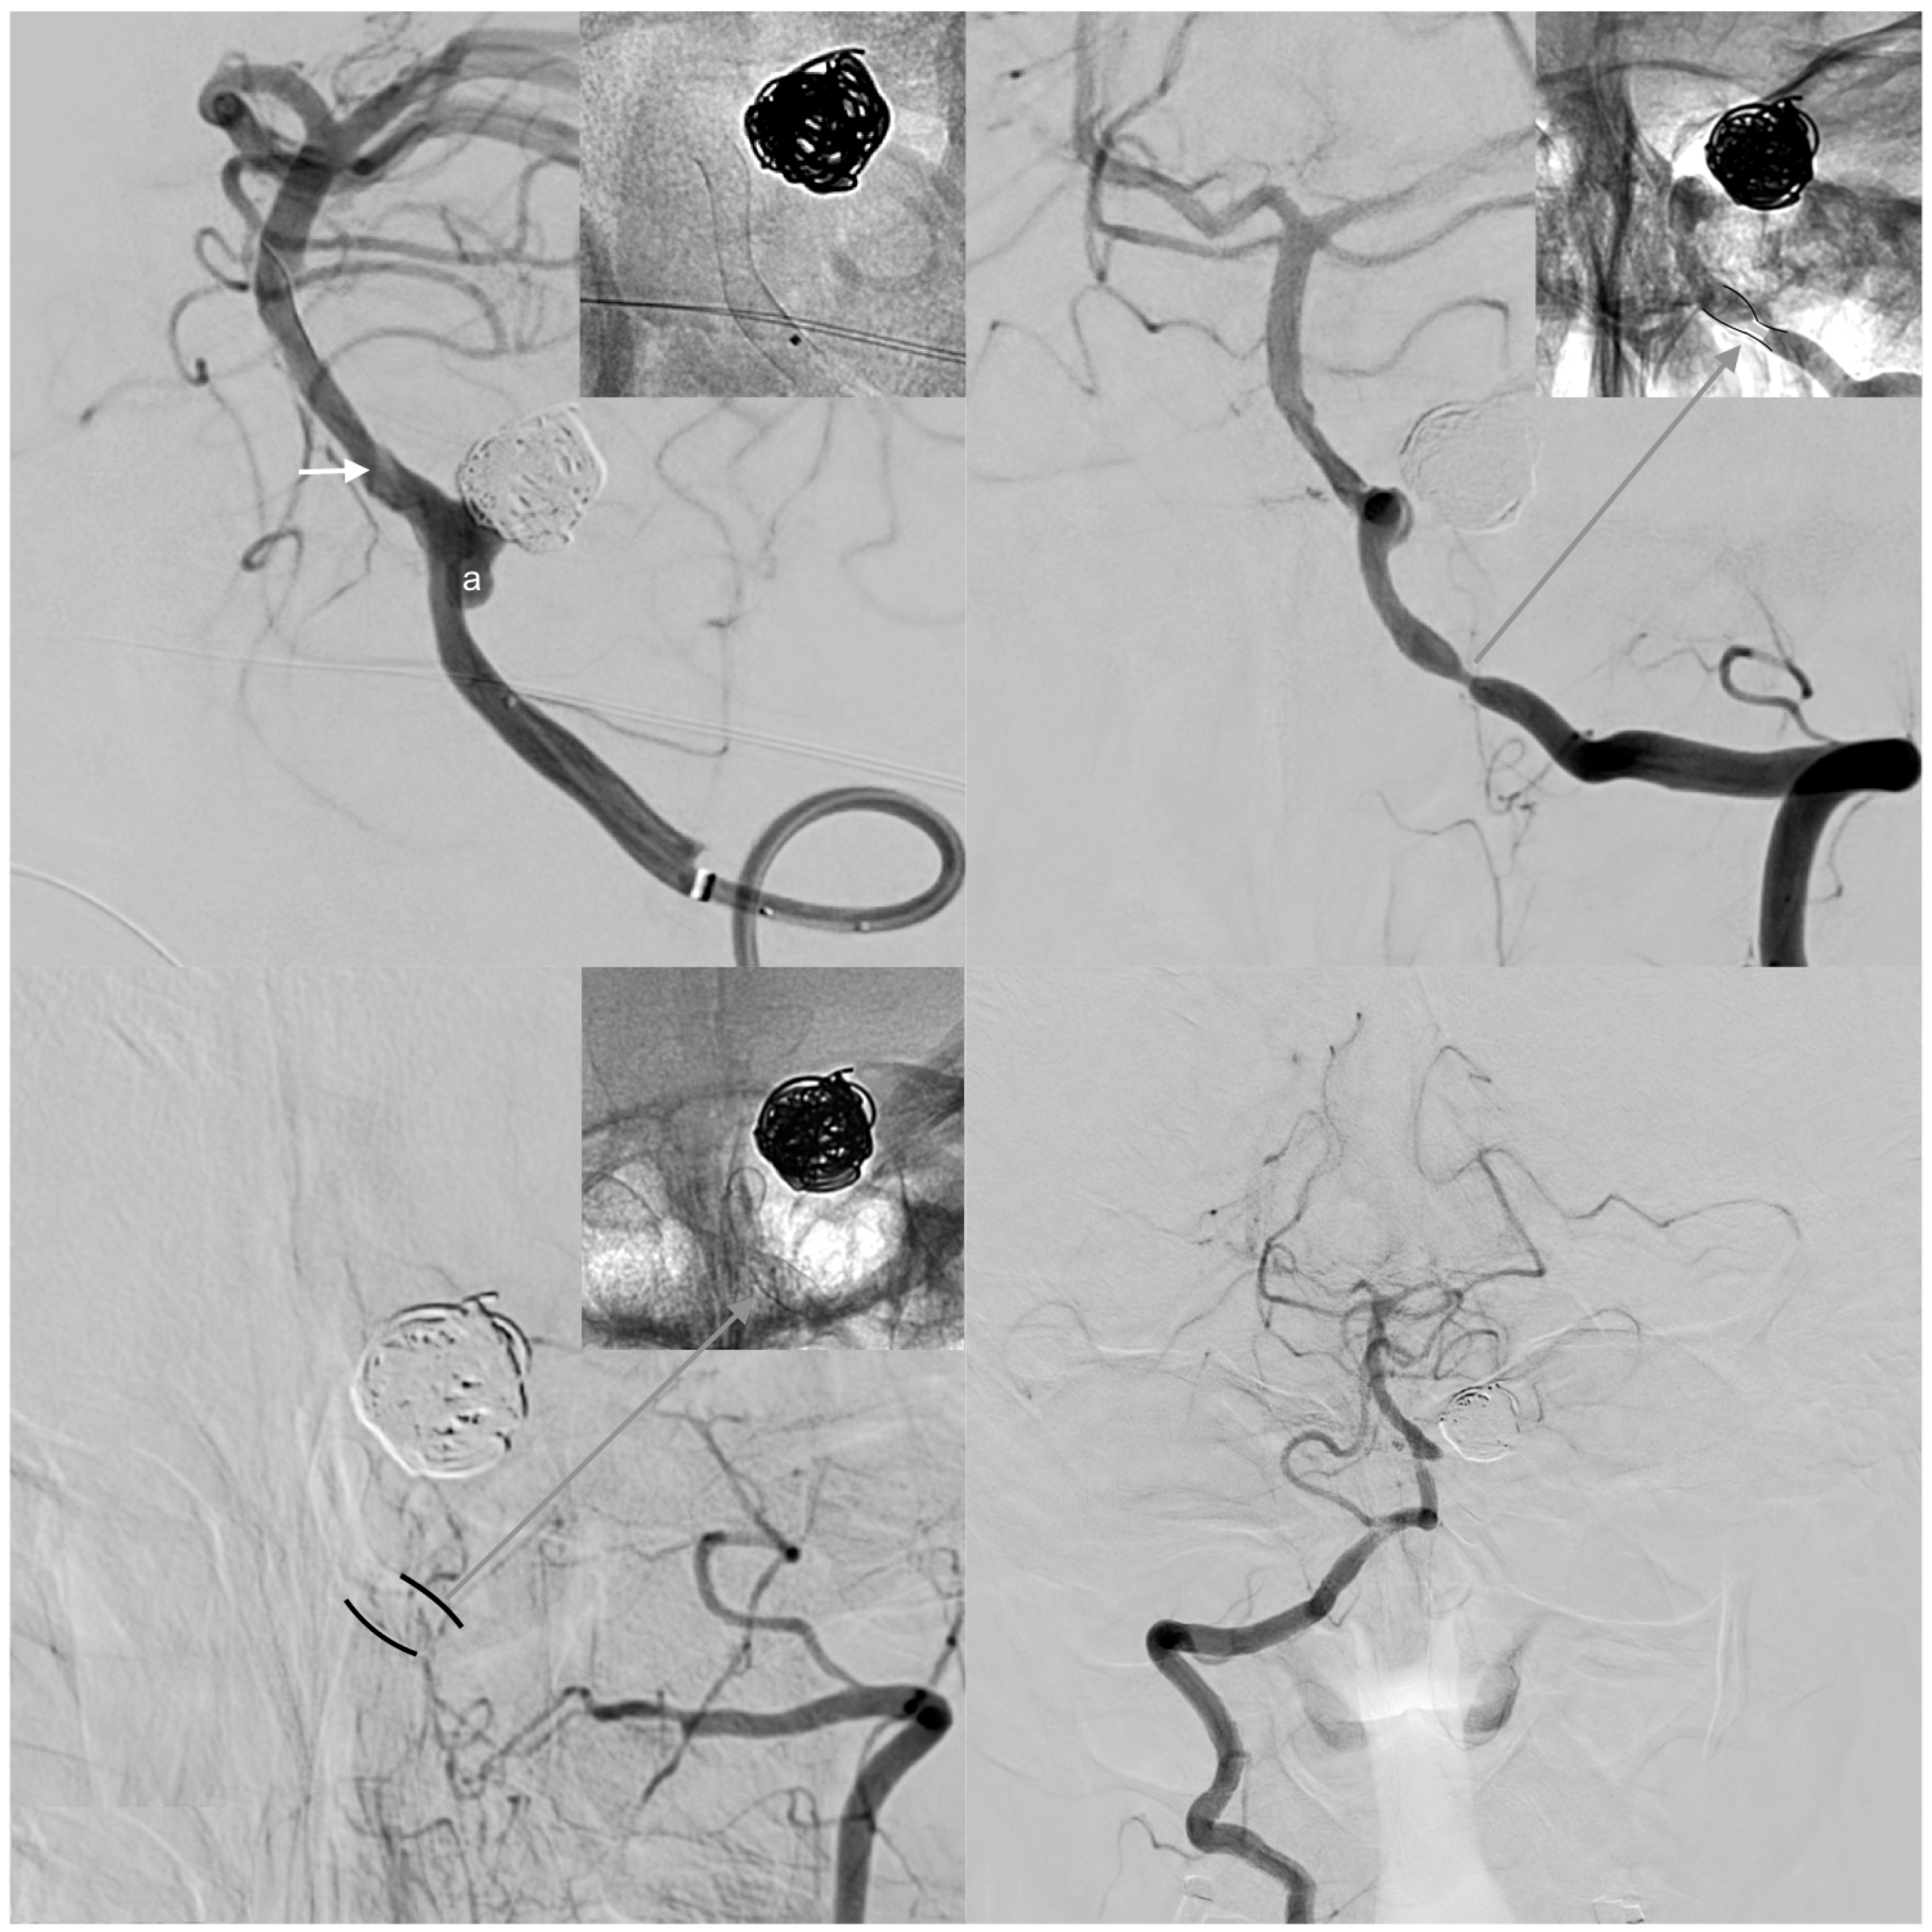

| 27 | Female | 27 | Left M1, ruptured saccular aneurysm, P&P | 3.5 | 2.8 | SVB 3.25 × 20 | 0.45 mm, 16% | >85% of the proximal (ICA) and >60% of the distal landing zone (M1) | 3 weeks | 10% | >95% |